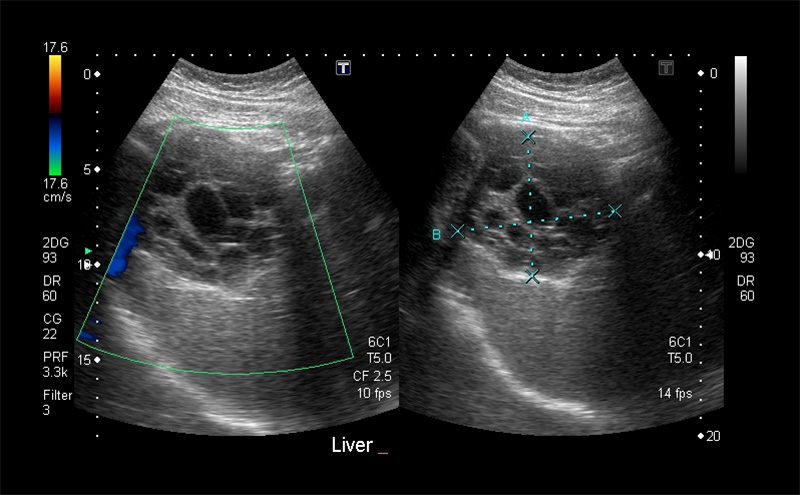

Figure 11. Normal Liver as seen from the right flank coronal view. Note the smooth surface, fine homogenous texture, and tubular vascular structures. The normal anterior-posterior diameter in the mid-clavicular line sagittal plane is between 12-14cm (A). The normal maximum dimension is from anteroinferior to posterosuperior is <16cm (B).

Figures 24B & 24C. Large pyogenic liver abscess with heterogenous material swirling inside the lesion, measuring >11cm in the long dimension (B) and >5cm in the shorter dimension (C).